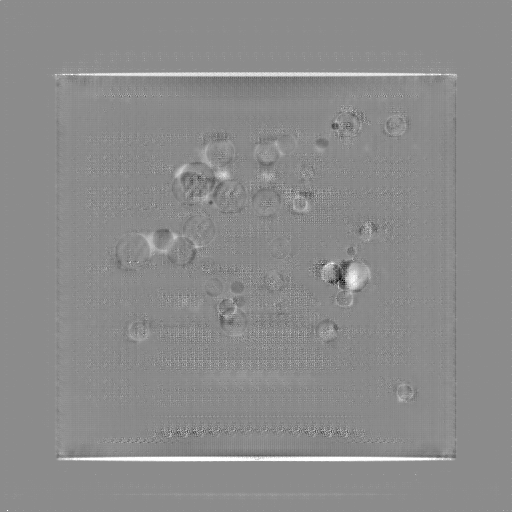

5.4 Real Knee Data with Metal Implants

Refer to caption

Figure 13: Three examples of synthetic perspective projection images for training, intensity window: [0, 4]. The appearance (e.g., image contrast and metal image resolution) of such DRR training images is different from that of real projection images in Fig. 14.